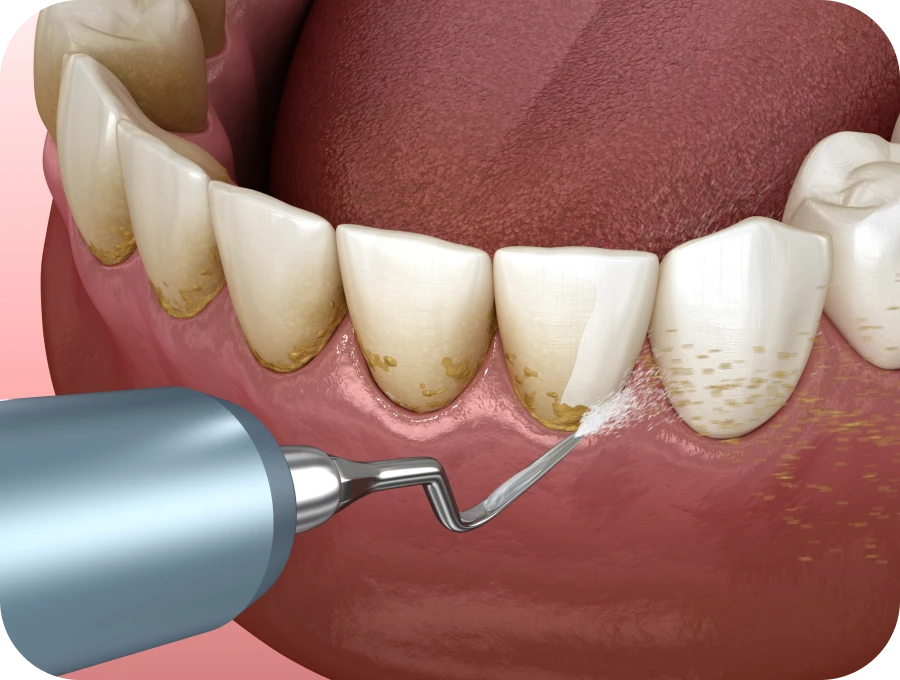

Les traitements comprennent généralement le détartrage en profondeur, le surfaçage radiculaire, la désinfection des poches parodontales et des conseils personnalisés d’hygiène. En collaboration avec nos spécialistes, vous bénéficierez d’un suivi adapté à votre situation pour retrouver un sourire sain et durable.